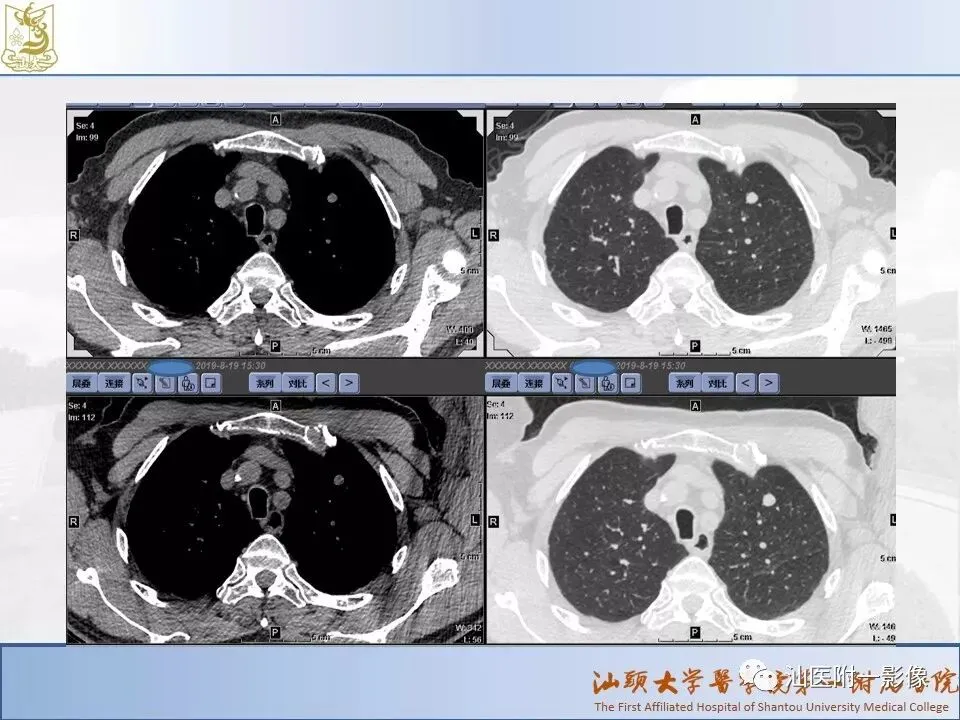

肺结节分类、处理及浅识肺结节分类影像报告和数据系统(Lung-RADS)

来源:汕医附一影像

说明:本课程病例主要来源于本院病例及参考资料,

无涉及病人隐私,仅做教学用途。